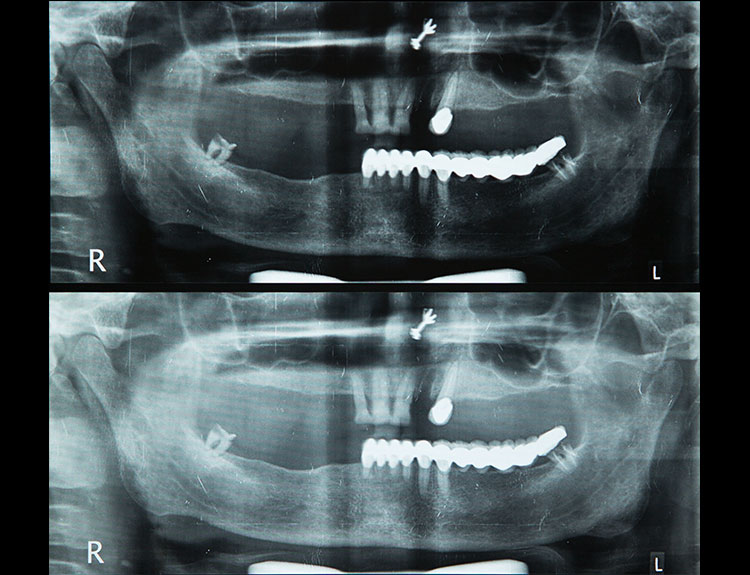

Dental implants are artificial tooth roots made of medical-grade titanium that are surgically placed into the jawbone. Once the implant integrates with the bone, a crown is fixed on top, giving you a strong, natural-looking replacement tooth.